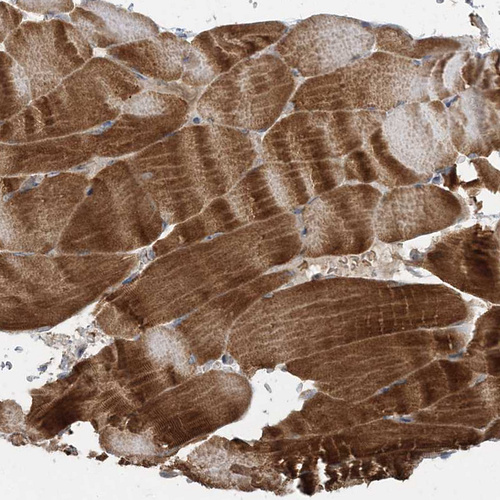

Immunohistochemical staining of human cerebellum, gastrointestinal, kidney and skeletal muscle using Anti-LRPPRC antibody HPA036408 (A) shows similar protein distribution across tissues to independent antibody HPA036409 (B).